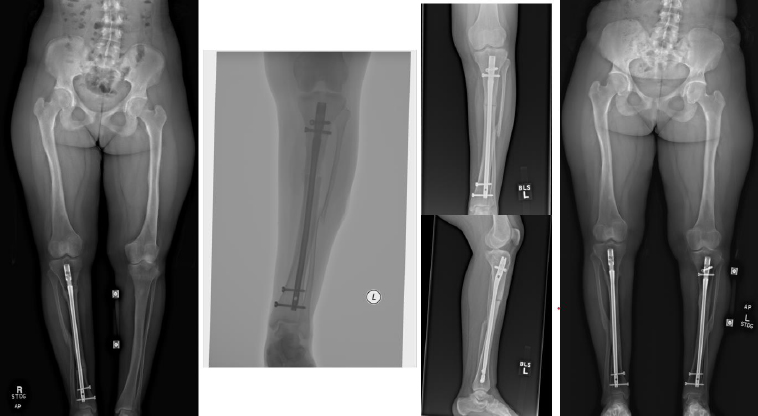

Complications occurred in 5 patients with tibial DC, including 3 cases of hardware removal due to symptomatic prominent interlocking screws and 1 case of delayed union. Complications arose in 4 patients with femoral DC, including 3 cases of nonunion, 1 case of hardware removal due to prominent screws, and 1 case of nonunion and infection (Table 1). There were no cases of peroneal nerve palsy or compartment syndrome. All patients achieved eventual clinical and radiographic union. Pre- and postoperative radiographs of 4 cases are included to highlight the variation in presentation and operative site (Figs. 4-7).

From left to right: Preoperatively, immediately postoperatively, 5 months postoperatively, and 5 years postoperatively (patient #7).

From left to right: Preoperatively, immediately postoperatively, 3 months postoperatively, 9 months postoperatively, and 3 years postoperatively (patient #8).